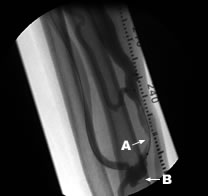

Aシャント血管瘤 Bシャント吻合部

シャント血管がこぶ状に膨らんだ状態をシャント血管瘤といいます。人工血管内シャントにも仮性血管瘤という同じような瘤が出来る場合も有ります。血管瘤は、こぶの皮膚が薄くなったり、痛み、感染、急速に拡大したりすれば手術が必要となります。